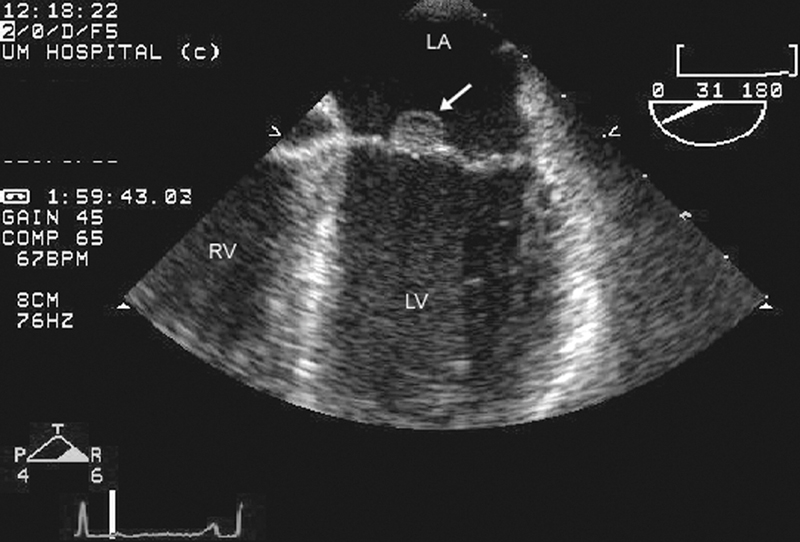

فحوصات تشخيصية لبعض امراض القلب والشرايين التاجية